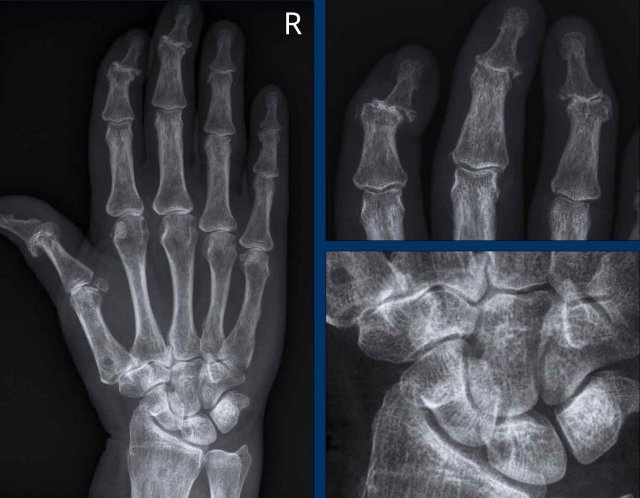

SLE: Z-thumbs and swan neck fingers SLE: Z-thumbs and swan neck fingers

Z-thumbs and swan neck fingers in a patient with SLE.

The deformities are thought to be a consequence of low-grade inflammation of the synovial membrane and capsule resulting in ligamentous laxity and muscular contracture.

Swan neck deformity

Here another example with extensive alignment deformities without erosions or signs of cartilage damage in a patient with SLE.

Another patient with a swan neck deformity.

Usually this is reversible in the early stage of the disease.